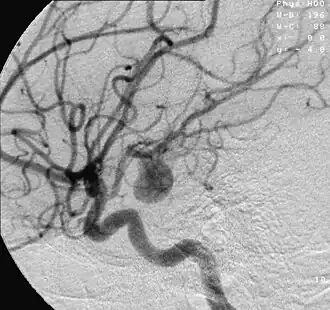

![]() Красным обведена указана область разрыва сердца | |